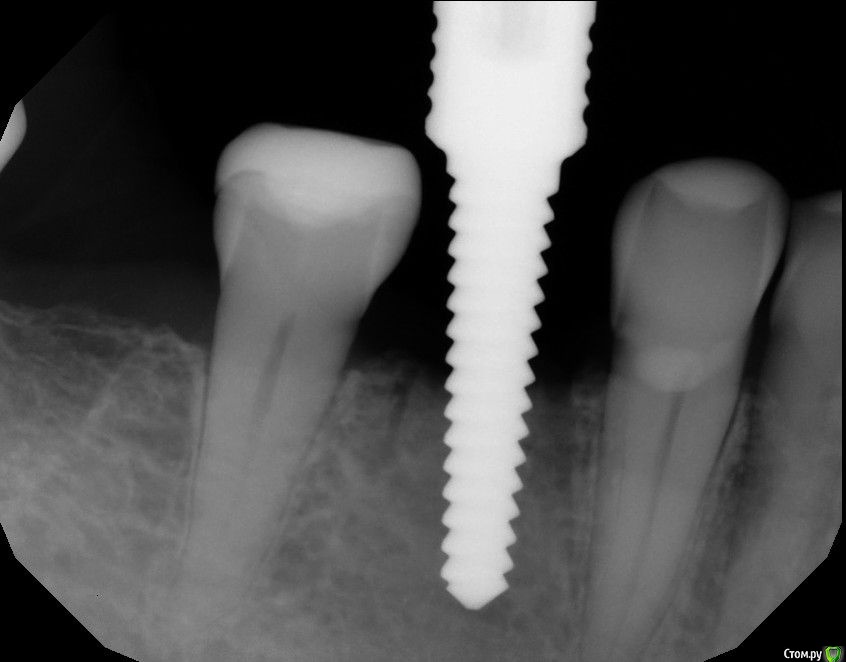

Astronaft Опубликовано 25 января, 2021 Автор Поделиться Опубликовано 25 января, 2021 Спасибо.День операции, 12 недель, день цементировки. 3 1 Ссылка на комментарий

Astronaft Опубликовано 24 января, 2021 Поделиться Опубликовано 24 января, 2021 (изменено) Одиночный цирнокиевый имплантат и расщепление без графта. Пациентка:тонкая хрупкая женщина 55 лет, сконцентрированная на своем здоровье, в некоторой мере мнительная.всегда тяжелые заживления после удалений (по опросам)есть результаты Клиффорд теста (такая книжка под 200 страниц с in vitro аллерго-пробами на все известные материалы) Поставленная цель:только цирконий Мне было интересно найти вариант найболее приемленый пациентке и мне. С минимом хирургического риска и риском сожаления пациентки про выбор костного материала. Во-первых, я не использую аллографты - философски, чужие протеины, неприятный запах - просто основываясь на своем мнении.Во-вторых, мнительные пациенты склонны "пойти и почитать" до или потом и как следствие внушить себе вещи которых может и не было. Но по скольку мысль материальна... Все обсудил заранее.План: ридж сплит (расщепление), имплантат без графта, свободный СТ графт; если случается вестибулярная рецессия - пилим зирконий во рту. Ридж сплит сделан пьезотомом - крестальный и вертикальные пропилы на глубины около 8-10мм.Пилотное сверло.Развдвинул кость остеотомами от 1.6мм до 3.5мм в диаметре.Очень мягкая кость - напомнила мегкую максиллу плотности ногтевой пластинки вестибулярно.Имплант встал легко, но торк 40нсм. СТ графт из области 18. Деэпителизирую скальпелем уже потом. Тут интересно отметить, что я перестал боятся ошметков эпителия.Пончо сверху имплантата (а-ля шашлык Карлоса).Швы. PTFE всегда хорош. 12 недель.Красивая десна.Периотест -5.8 - отличный результат.Оттиск. Циркониевая коронка симметричная другой стороне. Изменено 24 января, 2021 пользователем Astronaft 19 Ссылка на комментарий